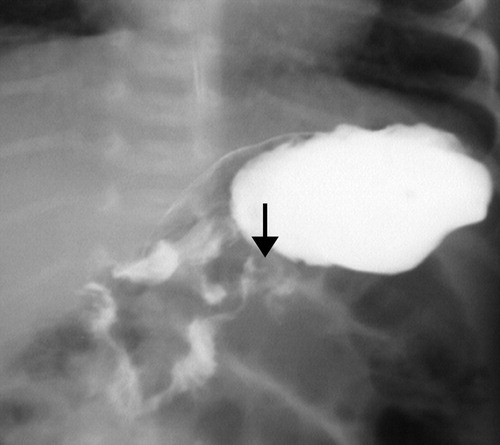

Fluoroscopic Signs of Midgut Volvulus

| Corkscrew sign | Spiral/twisting course of D3 and proximal jejunum — most classic sign |

| Beaking | Transitional tapering between D2 and D3; partial or complete obstruction |

| Proximal dilatation | Dilation of the duodenal bulb and D2 with hold-up of contrast |

Corkscrew sign may only be visible on one view. Always assess the duodenum on both frontal and lateral projections before concluding the study is normal. In partial volvulus, contrast may pass with a minimal twist — subtle beaking or rightward DJJ position may be the only clue.